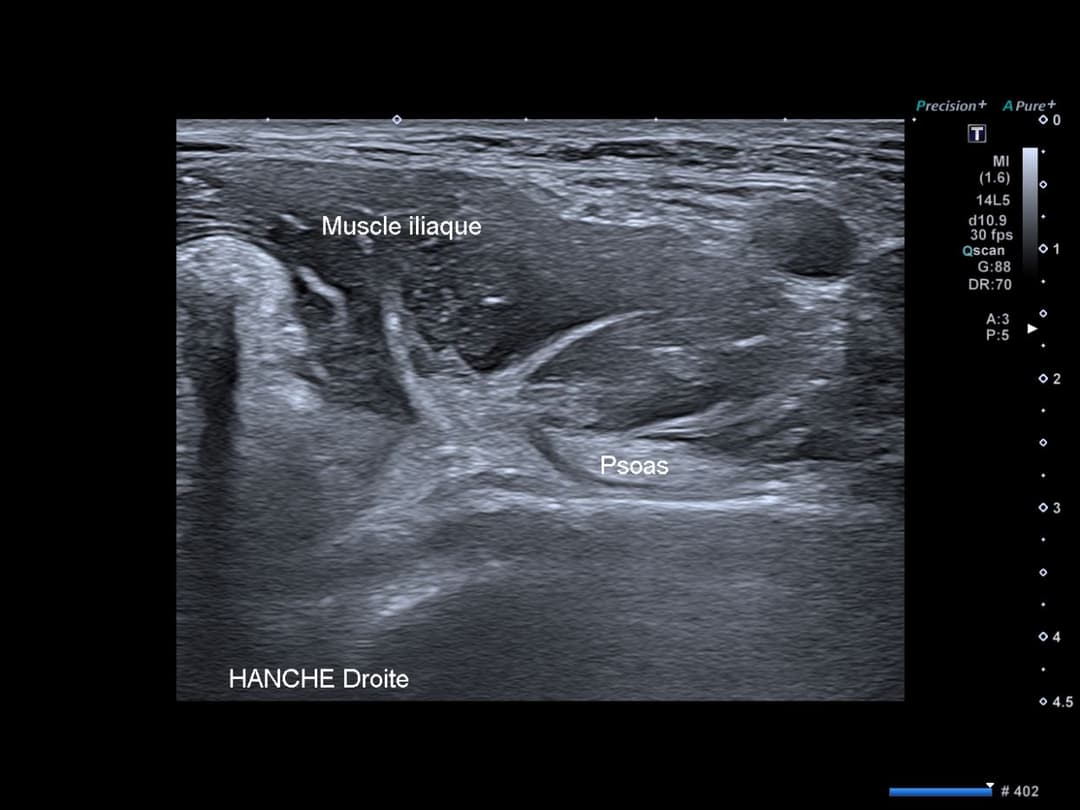

L'échographie dynamique est l'examen de référence pour le diagnostic du ressaut du psoas.

La technique consiste à placer la sonde en position transverse oblique sur la face antérieure de la hanche, au niveau de la réflexion du psoas sur la branche ilio-pubienne. L'examen se déroule en deux temps:

- En position de "grenouille" (flexion, abduction, rotation externe), le tendon du psoas est visualisé latéralement, avec une portion du muscle iliaque interposée entre le tendon et l'os (transposition antérieure).

- Lors du retour en extension, l'échographie permet d'observer le mouvement brusque du tendon qui "claque" contre la branche ischio-pubienne, libérant la portion musculaire piégée.

En étude dynamique, transposition antérieure du tendon distal du psoas en flexion rotation externe de hanche, puis "claquement" du tendon contre la branche ilio-pubienne lors du retour en extension.

Examen en étude statique normal